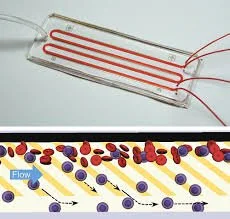

The research at the Bose Lab lies at the interface of biomaterial science, cellular engineering, and drug delivery with the aim of creating next-generation cell-based therapies for a wide range of human diseases. The lab combines multiscale device fabrication, material chemistry, and cell engineering principles to develop platform technologies capable of delivering precise doses of drugs (biologics) at the right location in the body at the right time. These platforms have applications in treating chronic diseases such as diabetes and liver failure, immune engineering applications in cancer and autoimmunity, and regenerative medicine.

“The Bose laboratory combines multiscale device fabrication, material chemistry, and molecular and cell engineering principles to gain insights into fundamentals of cellular interactions and apply these discoveries to design effective cell-based therapies”